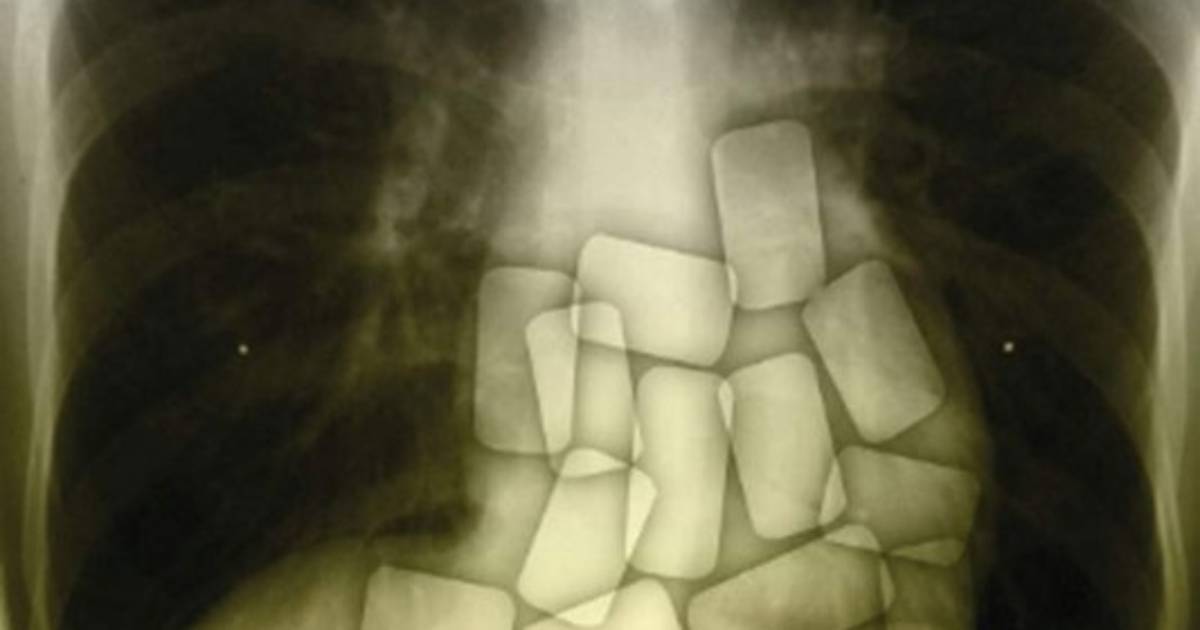

Bajo la supervisión de los traficantes, Bernardo ingería las cápsulas de cocaína en un apartamento en Burgos (norte de España), para ser transportado en un vehículo hasta Suiza, donde expulsaba la droga.

Pero en julio de 2014, 'cuando ya llevaba 67 cápsulas ingeridas, Fernando comenzó a sentirse mal' y 'comenzó a vomitar y tener convulsiones', pero la pareja que lo vigilaba no pidió asistencia médica, sino que se limitó a notificar al jefe, según el auto.